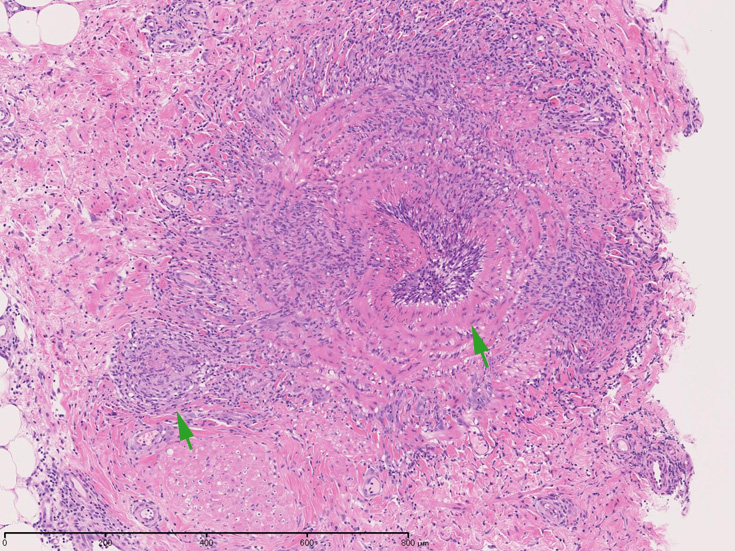

皮膚の血管(静脈・細動脈)病変、脂肪織炎 (サムネイルをクリックすると大きな画像が見られます)

Bec01.jpg

fibrinoidnecrosis01.jpg

vasculitisYa.jpg

fibrinoid necrosis

obstruction.jpg

Bec05.jpg

免疫染色:血管腔を閉塞する細胞の多くはCD68, CD163陽性細胞. CD34陽性内皮が保たれている。